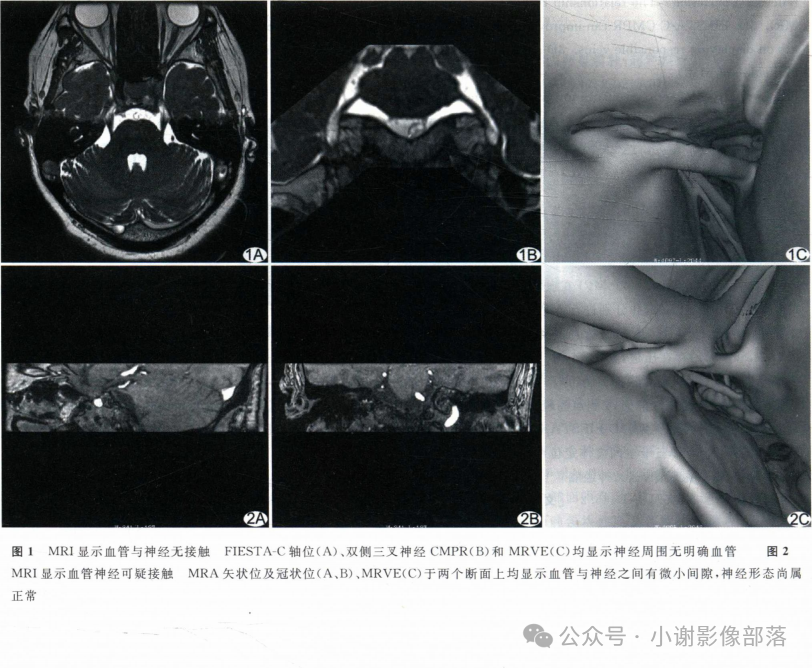

MR是目前诊断面肌痉挛及三叉神经痛的主要检查手段。

T2-TSE3D-RST-TRA成像是重T2成像,脑脊液呈高信号,三叉神经,面听神经和血管在脑脊液的高信号衬托下呈低信号可清晰显示,即使周围很小的血管分支也可能成像。

此外,T2-TSE3D-RST-TRA能对静脉以低信号成像,而且无须造影剂,通过多层面分析可确定压迫血管的来源,与常规磁共振技术相比不仅扫描速度成倍提高,并且通过三维薄层技术弥补对比度和分辨率的损失,获得高分辨率、高信噪比的图像,是检查脑神经和血管成像的最佳技术。